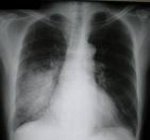

Поставлен диагноз двустороннее воспаление легких. Есть основоной диагноз хронический миеломоноцитарный лейкоз. До стационара дома 6 дней принимали Флоксиум в таблетках. В стационаре принимали 6 дней внутривенно цефтриаксон 2 раза в сутки. Потом 10 дней Авелокс в таблетках, потом еще неделю в таблетках Метронидазол и Кларитромицин. При прослушивании и по самочувствию лучше (остались сухие хрипы справа, а изначально "булькало" везде). Антибиотики отменены все. Но вот по рентгену улучшений никаких не видно (делали рентген через 2 недели после начала лечения. Заключение рентгенолога "продолжать лечение". Но врач говорит, что рентген не отличает воспаление от фиброзных уплотнений. Вот это как раз и смущает. Ну хоть какое-то улучшение должно быть на рентгене видны..А он одинаков. Слышала, также, что рентген может "отставать" тот клинической картины...Так ли это? Что посоветуете в данной ситуации? Боюсь, чтоб не было недолеченного воспаления.